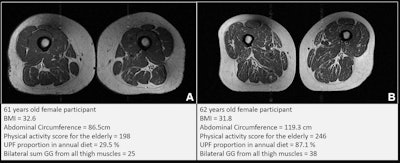

Representative axial T1-weighted spin-echo thigh MRI scans in (A) a 61-year-old female participant and (B) a 62-year-old female participant. Both participants were of similar age and body mass index (BMI, calculated as weight in kilograms divided by height in meters squared). Both had Physical Activity Scale for the Elderly scores above the mean score in the study. According to the World Health Organization definition, the participant in B qualified as having abdominal obesity (abdominal circumference ≥ 88 cm). Abdominal circumference is a measure of central obesity that captures fat distribution and serves as an indicator of cardiometabolic health. Compared with the participant in A, the participant in B had a higher proportion of ultra-processed food (UPF) in their diet (87.1% vs 29.5%) and exhibited fattier thigh muscles bilaterally, with Goutallier grade (GG) for all thigh muscles summing to 25 for the participant in A and 38 for the participant in B.Representative axial T1-weighted spin-echo thigh MRI scans in (A) a 61-year-old female participant and (B) a 62-year-old female participant. Both participants were of similar age and body mass index (BMI, calculated as weight in kilograms divided by height in meters squared). Both had Physical Activity Scale for the Elderly scores above the mean score in the study. According to the World Health Organization definition, the participant in B qualified as having abdominal obesity (abdominal circumference ≥ 88 cm). Abdominal circumference is a measure of central obesity that captures fat distribution and serves as an indicator of cardiometabolic health. Compared with the participant in A, the participant in B had a higher proportion of ultra-processed food (UPF) in their diet (87.1% vs 29.5%) and exhibited fattier thigh muscles bilaterally, with Goutallier grade (GG) for all thigh muscles summing to 25 for the participant in A and 38 for the participant in B.RSNA